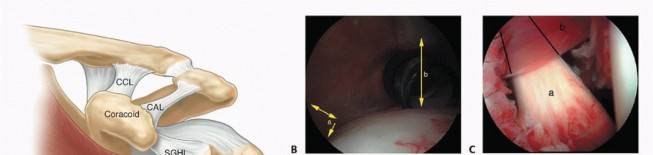

Arthroscopic Capsular Releases for Loss of Motion DEFINITION Shoulder stiffness can be a function of soft tis…